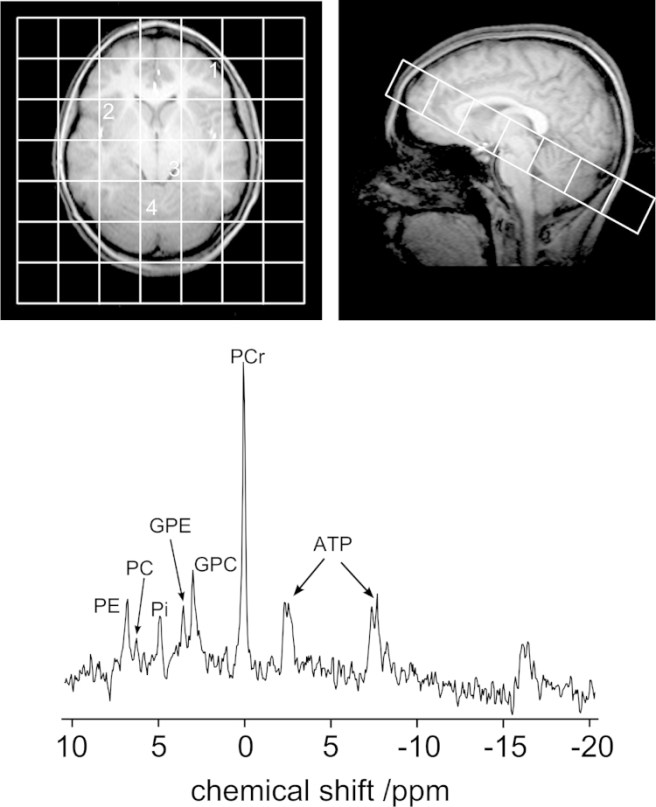

31P-MRS (or 31phosphorous magnetic resonance spectroscopy) is a magnetic resonance-based form of imaging that is used to measure and quantify the function of the mitochondria. It will allow the researchers to assess whether the drug is successfully normalising the function of mitochondria in regions of the brain affected by Parkinson’s. For the participants the experience of 31P MRS will be exactly the same as having a normal MRI scan – you lie there in the machine thinking happy thoughts.

31P MRI-Spectroscopy. Source: PMC